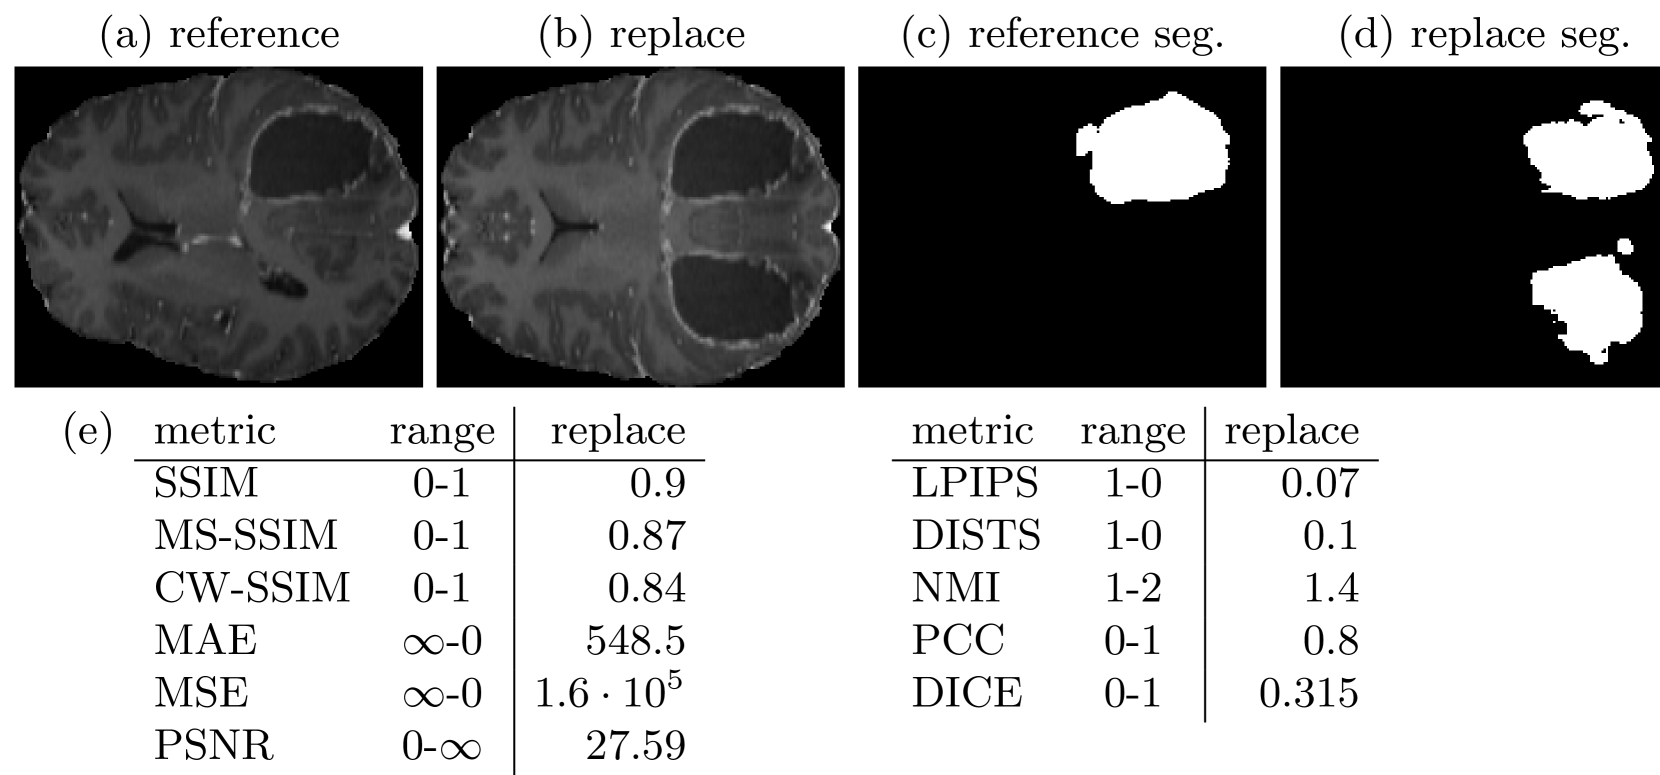

Similar to the masking, for medical imaging, a possible tumor is probably one of the most important structures to be correctly synthesized in an MR image of the human brain. However, if there is only a mask of the tumor in the reference image, artificially synthesized tumors in healthy tissue regions in the synthetic image are easily overlooked. Tumors may also be very heterogeneous in their texture and local structure, such that similarity metrics restricted to the tumor region are not informative about the similarity of the tumor type. Therefore, it can be useful to define and perform an important downstream task with the synthetic images. Then the similarity of the synthetic images to the reference images can be assessed by comparing the performance of the downstream task results of both image subsets. If both images lead to very similar results, the synthetic and the reference image appear similar regarding the tested task. In this case, we trained an automatically configuring U-Net based segmentation network [19, 20] on the T1c images of the BraSyn dataset[17] and the whole tumor annotations. The architecture of the U-Net included five residual blocks, with downsampling factors 1, 2, 2, 4 and 4, initially 32 features and one output channel activated by a sigmoid function. As a preprocessing step for training and inference, Zscore normalization was applied to the input images. In Fig. 5 example segmentations are shown and in addition to the previous metrics, the DICE score was assessed from the segmentation results. Especially compared to SSIM, the extra or missing tumors are clearly detected by the DICE score.

Figure 5: An example of a reference image (a) and a version with replacements (b), as well as their respective tumor segmentations (c, d) are shown. Specifically, the lower half of the reference images are replaced by the mirrored upper half. The mean similarity scores over 100 images are assessed by different metrics (e). While most similarity metrics hardly change with artificial introduction or removal of a tumor, additional or missing tumor segmentations strongly decrease the DICE score.